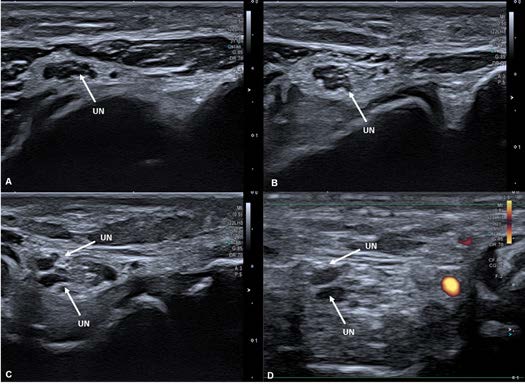

A 45-year-old woman, housekeeper, was sent to the Rheumatology appointment for pain and functional limitation in extension and flexion movements of the fingers, accompanied numbness in the 4th and 5th finger of the right hand. This clinical depiction had 2,5 years of evolution, with progressive worsening. The physical exam showed pain at palpation of ulnar nerve in the ulnar fossa of the right elbow. Blood tests and electromyography studies did not show any significant changes. Ultrasonography of the elbow revealed no changes of the median and radial nerves. The Ulnar Nerve (UN) presented without any anomalies in its entire course, except being bipartite in a small portion immediately proximal to the ulnar fossa, returning then to its unique configuration. (Fig. 1). This anatomic variation was then confirmed by Magnetic Resonance Imaging (MRI) as illustrated in Figure 2. The patient was referred to Plastic Surgery and submitted to an ulnar nerve surgical decompression at proximal level. Two weeks after surgery a sustained marked improvement of the numbness was confirmed.

Figure 1: Right Elbow Ultrasono- graphy Transverse Cut: Ulnar nerve at different levels of its course going distal to proximal (1A to 1D). It starts with its usual unique configuration (1A and 1B) and then starts to split (1C). Through Fig. 1D it is possible to distinguish the ulnar nerve (without Power Doppler signal) from blood vessels (with Power Doppler signal).